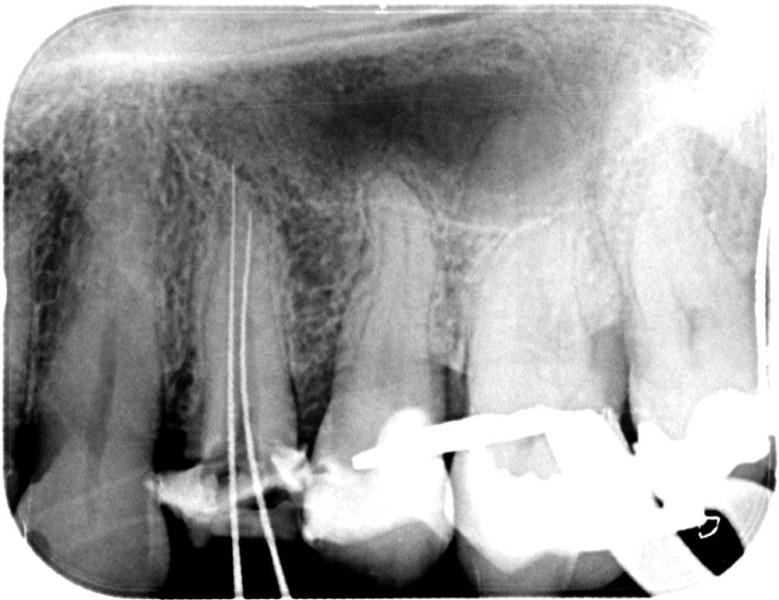

Molar retreatment